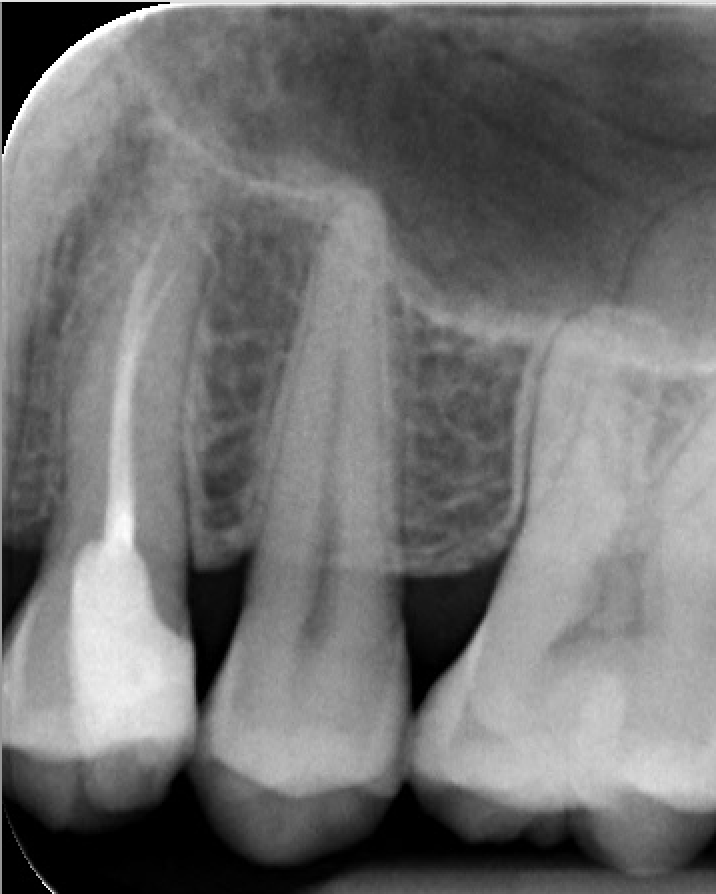

Hartelijk dank voor uw antwoord, het is zeer nuttig! Ja, ik begrijp dat je de prijs iets moet verhogen en vervolgens verlagen als dat nodig is. Het klinkt eerlijk en betrouwbaar. Toch vertelde mijn tandarts mij dat de x-foto goed is, dat de uiterst linker tand met gevulde wortel vanbinnen geen problemen heeft, en dat de behandeling zelf nu niet eens nodig is. Hij vertelde mij dat hij mij de rekening zou sturen als ik deze verkleuring, die je ziet op de foto die ik heb gemaakt, wil laten behandelen.

Een levend stuk hout kan je iets buigen, een dood stuk hout breekt als je dat buigt. Een wkb behandelde "dode" kies wordt broos vandaar dat ik een kroon adviseer. Ik wacht niet tot de kies breekt. Want als het ongunstig breekt dan is het verloren. Geld v d vullingen kan je beter stoppen in het tarief v e kroon. Kroon is helaas prijziger.

Hartelijk dank voor de tip, ik zal overwegen om meteen voor de kroon te gaan. Maar eerst wil ik er zeker van zijn dat ik deze tandarts kan vertrouwen, en wil ik controleren of de rekening die hij voorstelt eerlijk is. Op dit moment lijkt het erop dat hij wil proberen mij te veel in rekening te brengen.